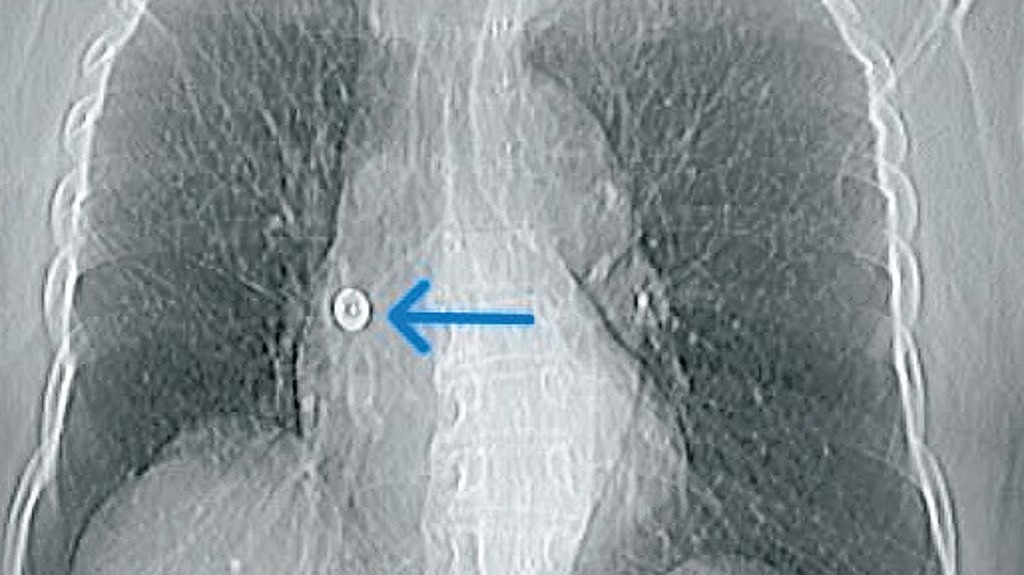

She later developed persistent dry cough and wheezing, but multiple hospital visits failed to identify the cause. The issue came to light only after doctors at Aster CMI Hospital conducted advanced imaging, including chest X-ray and CT scans, revealing the foreign object embedded in her lung.

Dr Sunil Kumar K, Lead Consultant – Interventional Pulmonologist at the hospital, explained that the pin’s sharp end had pierced into the lung, making removal with standard instruments risky. “The team used a Fogarty balloon to gently move it out and then pulled it out using special forceps, all done while the patient was under sedation,” TNIE quoted him as saying.